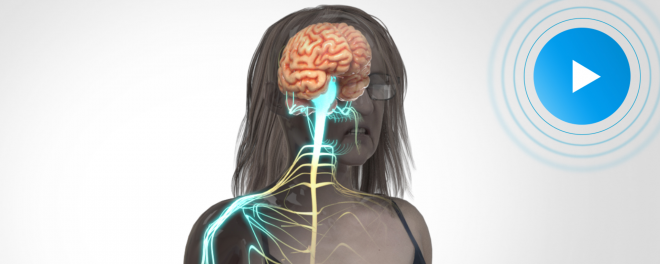

| WATCH THE VIDEO |

| Woman’s Slip-&-Fall Injuries Develop Into Complex Regional Pain Syndrome & Thoracic Outlet Syndrome |

A repairman dropped his toolbox in the middle of a Maine casino’s employee entranceway and stepped outside. Surveillance video captured a longtime employee entering moments later, greeting everyone with a smile as she had done for years. Tragically, she tripped over the toolbox, broke her right arm, and tore her rotator cuff. ... |

"DK Global are not only critical mission advisors, they're really strategic partners; they'll bring a really creative angle that you haven't brought to your case already; they'll help you develop strategies to make your presentation impactful, memorable, and repeatable." |

| Michael T. Bigos - Berman & Simmons |